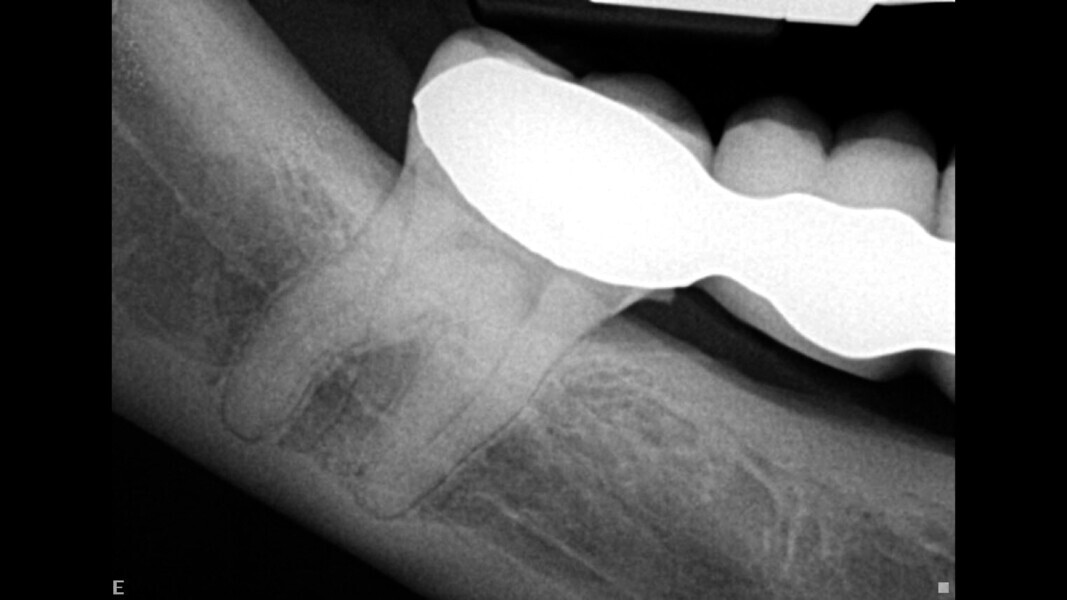

The third case highlights the artificial intelligence incorporated into DTX Studio Clinic, one feature of which is automatic tracing of the mandibular canal. In this case, it was a very helpful feature to have. The patient was suffering from irreversible pulpitis of a mandibular third molar. He wanted to save the tooth at any cost because did not want to have an implant (the molar was an abutment tooth for a bridge). The radiograph showed the roots of the molar overlapping the mandibular canal (Fig. 12). A 3D radiograph was taken, and on this, the software traced the mandibular canal overlapping the molar in the panoramic view. The endodontic mode revealed that the canal bypassed the buccal area, slightly touching the mesiobuccal canal (Figs. 13–15). The radiograph taken immediately after the root canal therapy, performed through the crown, showed complete obturation of all the canals (Fig. 16).